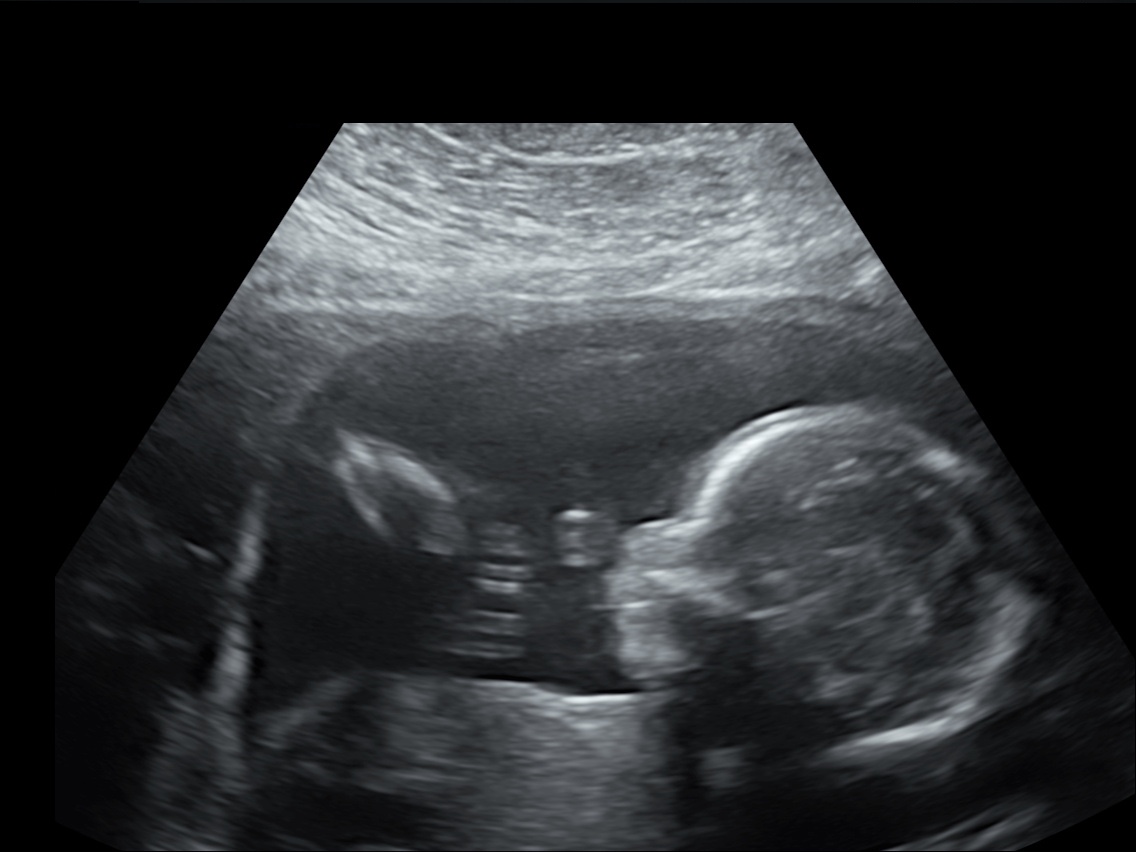

30 weken

Een echo na 30 weken.